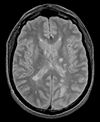

Slicer Registration Library Case 04: Multi-contrast brain MRI of Multiple Sclerosis

exam 1: PD exam 1: T2 exam 1: T1-Gd

This scenario occurs in many forms whenever we wish to assess change in a series of multi-contrast MRI. The follow-up scan(s) are to be aligned with the baseline, but also the different series within each exam need to be co-registered, since the subject may have moved between acquisitions. Hence we have a set of nested registrations. This particular exam features a dual echo scan (PD/T2), where the two structural scans are aligned by default. The post-contrast T1-GdDTPA scan however is not necessarily aligned with the dual echo. Also the post-contrast scan is taken with a clipped field of view (FOV) and a lower axial resolution, with 4mm slices and a 1mm gap (which we treat here as a de facto 5mm slice). read more about this dataset here

• reference/fixed : PD.1 baseline exam , 0.9375 x 0.9375 x 3 mm voxel size, axial acquisition, RAS orientation.

• fixed T2.1 baseline exam , 0.9375 x 0.9375 x 3 mm voxel size, axial acquisition, RAS orientation. -> (aligned with PD.1, not used for registering)

• moving: T1.1 (GdDTPA contrast-enhanced scan) baseline exam 0.9375 x 0.9375 x 5 mm voxel size, axial acquisition.